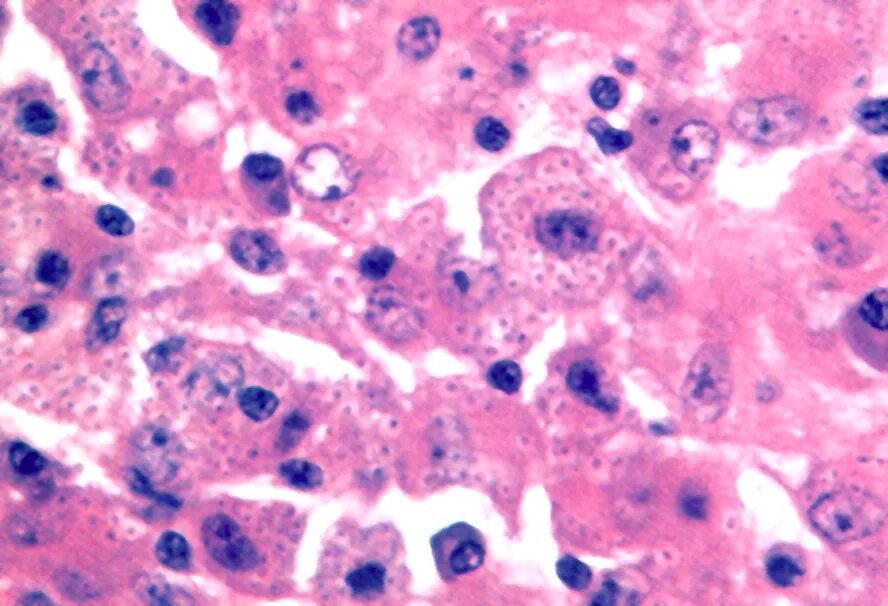

Гистоплазмоз это